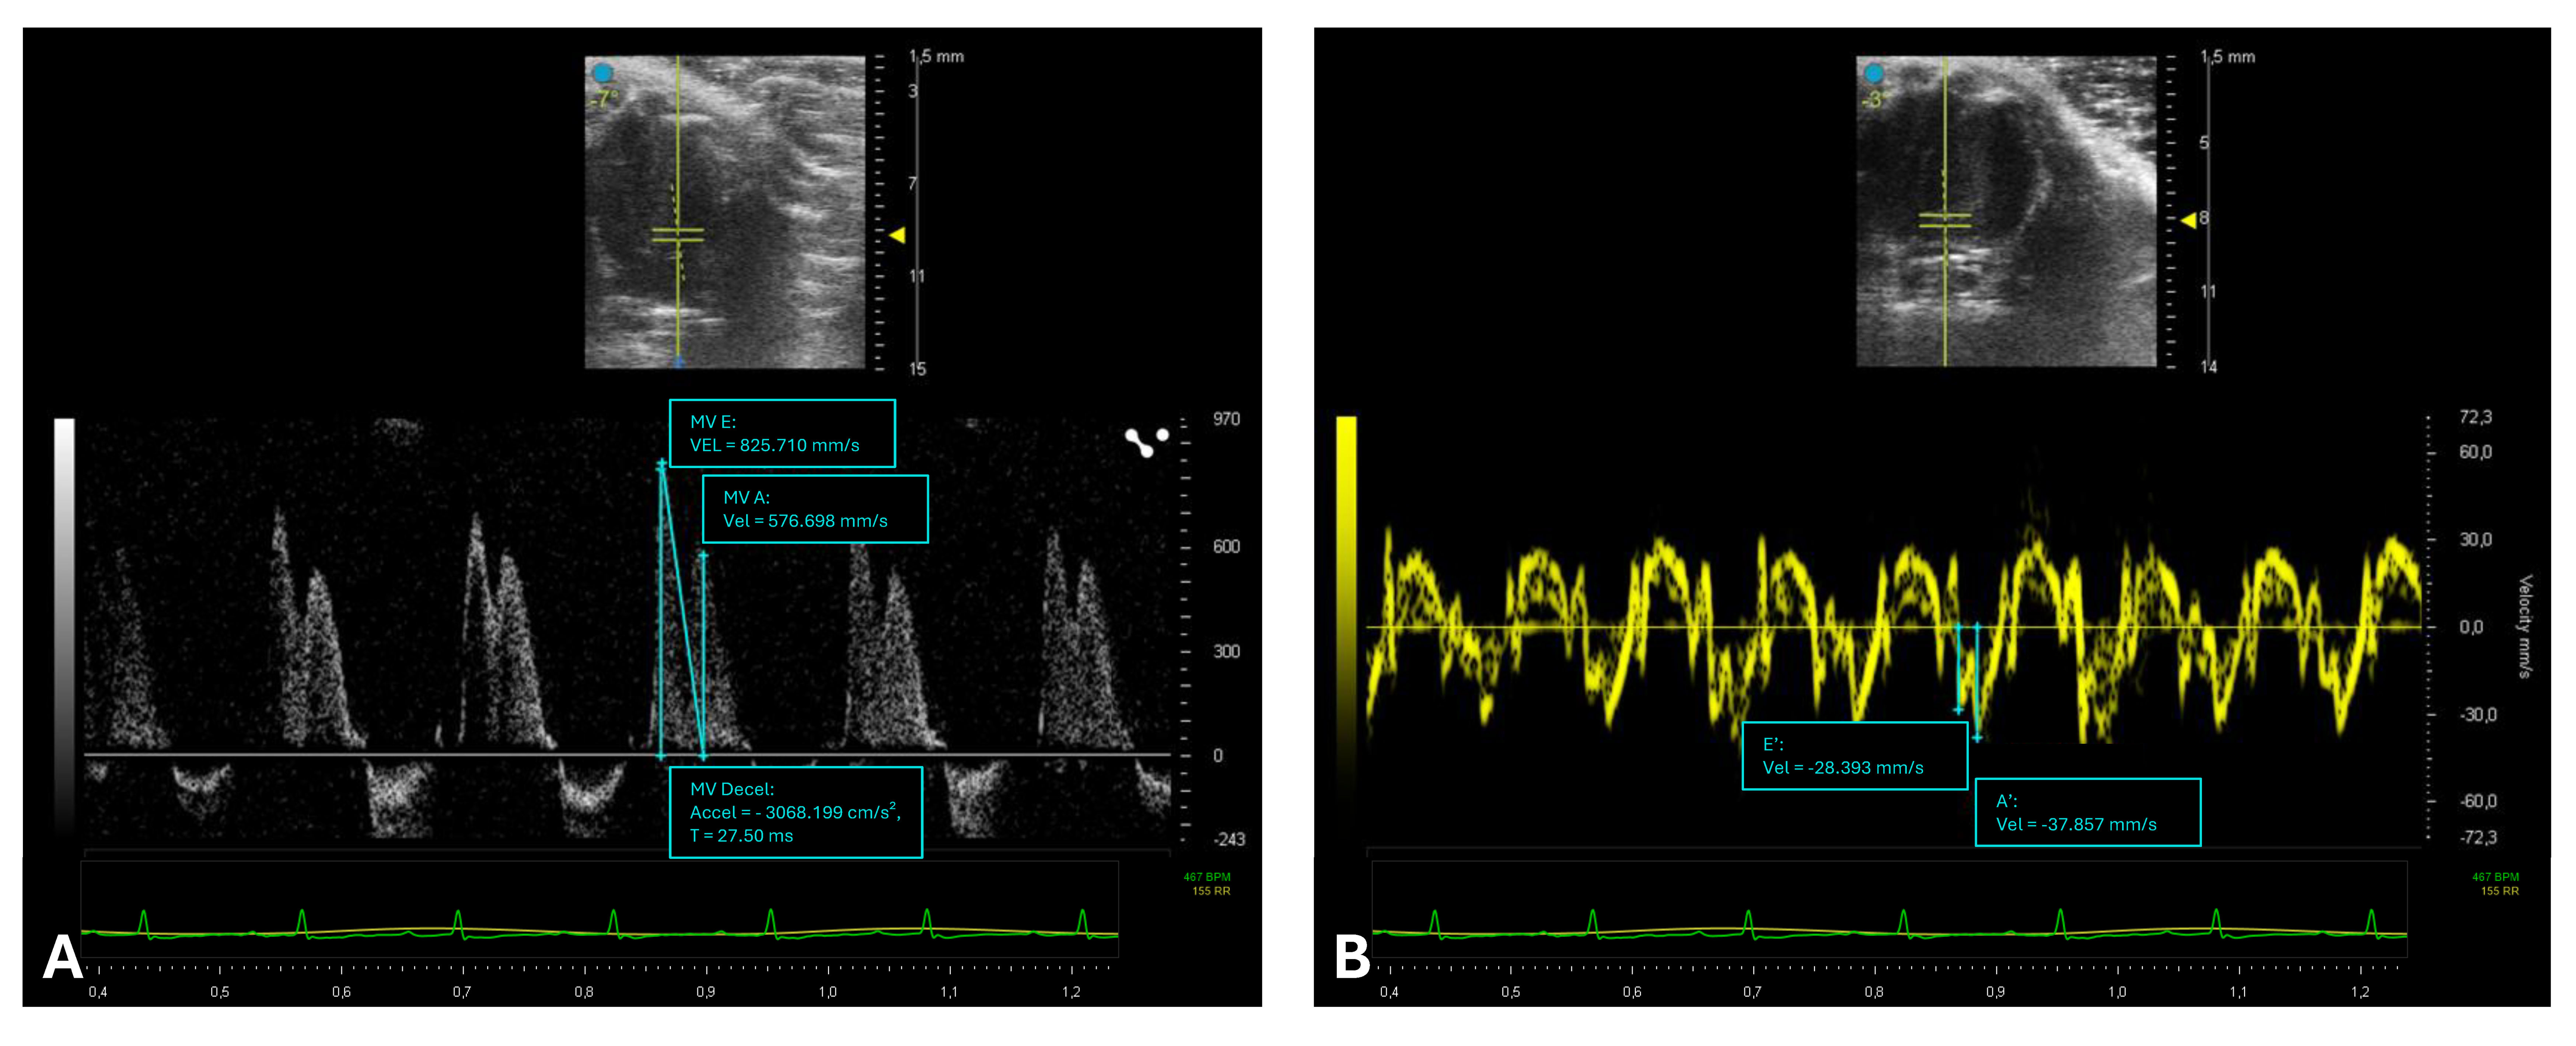

The assessment of diastolic function is a complex field, and the applicability of echocardiographic parameters commonly used in humans has not yet been extensively validated in various murine pathophysiological models (Figure 3) [34].

PWD of transmitral inflow allows for the measurement of E and A waves, their ratio (E/A), and the deceleration time (DT), reflecting LV relaxation and compliance. Impaired relaxation results in a reduced E wave and prolonged DT, whereas increased stiffness leads to steep E-wave deceleration and decreased A wave due to elevated filling pressures. Mixed diastolic dysfunction can show both patterns. Yang and colleagues were the first to investigate the effectiveness of transmitral Doppler echocardiography in assessing left ventricular diastolic function in mice [35]. To measure these parameters, an image of the mitral valve must be obtained in the A4C view (Figure 4).

Assessment of diastolic function in mice. This figure illustrates echocardiographic assessments of diastolic function in mice obtained from an apical four-chamber (A4C) view using pulsed-wave Doppler (PWD) and tissue Doppler imaging (TDI). (A) PWD capture transmitral flow velocities: early diastolic ventricular filling (E-wave), late diastolic ventricular filling due to atrial contribute (A-wave), and E-wave deceleration time (DT), reflecting diastolic relaxation and ventricular filling dynamics (diastasis). (B) TDI assesses myocardial tissue velocities at the mitral annulus level: early diastolic myocardial velocity (e′ wave) and late diastolic myocardial velocity (a′ wave), critical parameters for assessing myocardial relaxation properties and ventricular diastolic function.

The transducer should be positioned above the left side of the xiphoid, perpendicular to the central axis of the mouse’s body, rotated counterclockwise by approximately 45°, with a tilt of 30–60° relative to the platform. The Doppler spectrum of the mitral inflow can be easily recorded using the PWD mode. The sample volume is placed at the level of the mitral valve orifice, just beyond the valve leaflets, to measure the inflow into the LV during diastole, which displays an E (early diastolic ventricular filling) and an A (late diastolic filling due to atrial contraction) (Figure 4A) [36]. In addition to traditional Doppler indices such as mitral inflow velocities, parameters like the pulmonary venous blood flow waveform and left ventricular inflow propagation velocity obtained via the Color M mode have been demonstrated to provide complementary and valuable information on murine diastolic function. The pulmonary venous flow pattern reflects left atrial pressure and ventricular filling dynamics, offering insights that can help differentiate between normal and pathological diastolic states [35]. Similarly, the inflow propagation velocity is considered a less load-dependent marker of myocardial relaxation and has been shown to improve the accuracy of diastolic function assessment in mice [37,38]. However, it is important to note that these measurements require high-resolution echocardiographic equipment and technical expertise, given the small size and rapid heart rate of murine models. Consequently, their application may be limited in some settings. Nonetheless, incorporating these parameters into echocardiographic protocols enhances the comprehensiveness of diastolic function evaluation and is encouraged in studies investigating subtle or early cardiac dysfunction.

A more recent advancement in the assessment of diastolic function is TDI, a technique that allows for the direct analysis of myocardial velocities at the tissue level, as described well in a study by Schnelle and colleagues [20,39]. TDI is typically acquired at the lateral mitral annulus and provides insights into longitudinal myocardial motion. The resulting waveform typically displays two positive peaks during systole and two negative peaks during diastole: an early diastolic peak (e′) and a late diastolic peak (a′) (Figure 4B). The e′ peak is considered a robust index of myocardial relaxation. A reduced e′ suggests impaired ventricular relaxation and reduced early diastolic suction. Conversely, e′ may increase in states of elevated preload [40]. Importantly, the E/e′ ratio—obtained by dividing the transmitral E velocity by TDI-derived e′—is widely used to estimate LV filling pressures [41]. A high E/e′ ratio indicates elevated LA pressure and is associated with diastolic dysfunction [42].